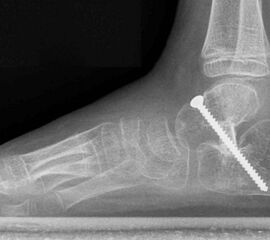

Röntgen Fuß AP und seitlich im Stand oder belastungssimuliert (Abb.1,2).

• Röntgenkontrolle (Bild 21,22).

• Röntgen des dargestellten Falles 3 Monate post OP (Bild 25,26)